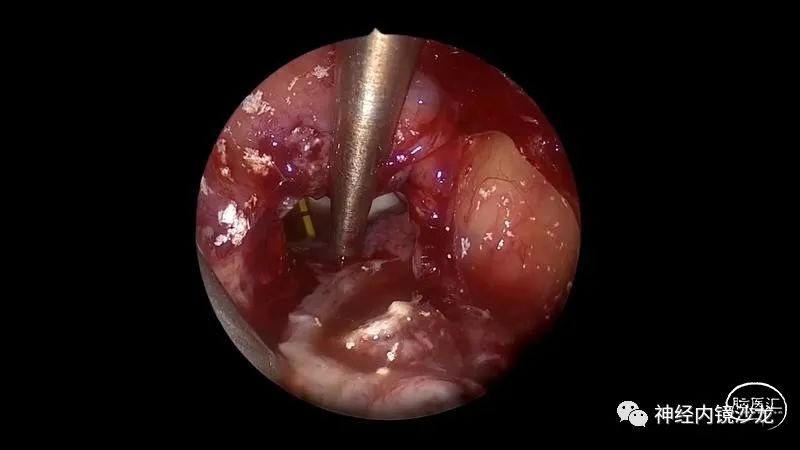

精彩图表

手术视频